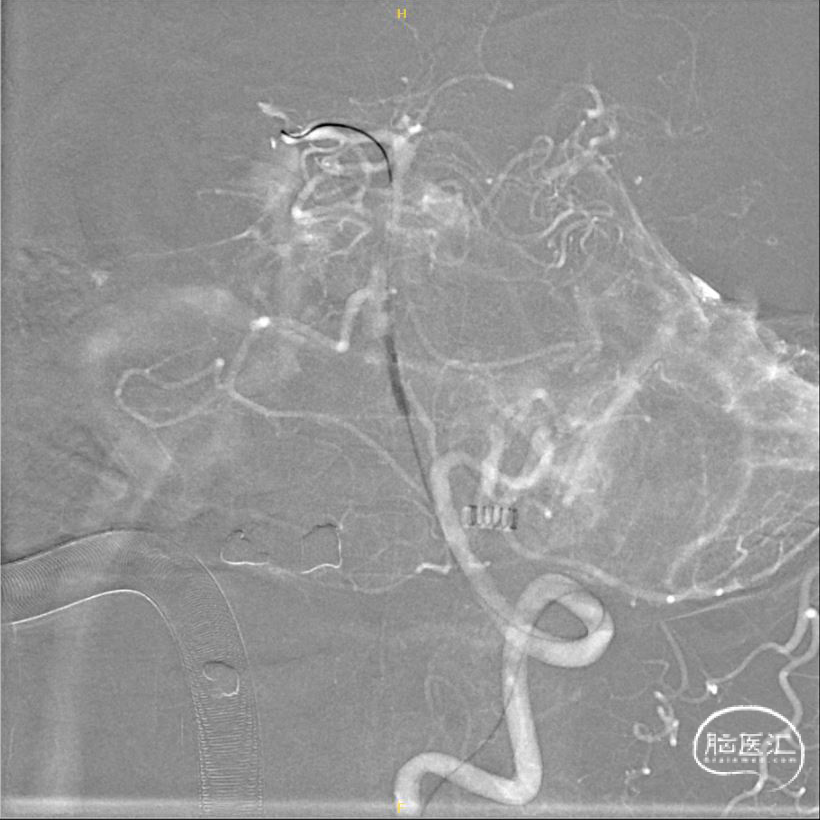

将8F 导引导管置于左侧锁骨下动脉,6F 115cm Navien中间导管置于左侧椎动脉V2段,调整工作角度,于路图下使用HYBRID 1214DA微导丝将SL-10微导管通过基底动脉狭窄段,并置于左侧大脑后动脉。

交换300cm Transend微导丝后,交换1.5*15mm Gateway球囊缓慢扩张。

交换3.0*15mm Wingspan支架,定位准确后释放,交换2.0*9mm Gateway球囊于支架内后扩张。

术后3D旋转造影。